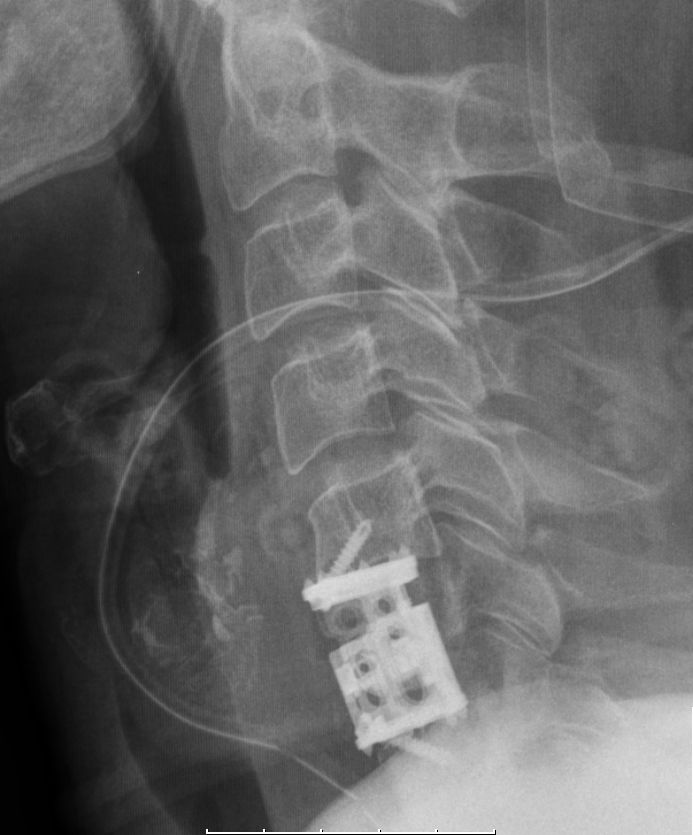

| Wirbelkörper - Ersatz |

CUP: Ersatz des 5. HWK durch Implantation eines ADDplus® (anterior distraction device)